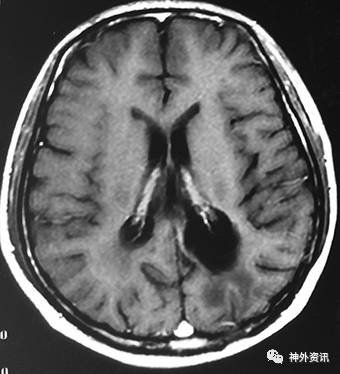

既往史:11年前(2005年)因“头痛1月”,行头颅MRI检查提示左顶枕肿瘤,胶质瘤?(图片未找到)收住我院,完善术前检查后行开颅肿瘤切除术。术后病理提示非霍奇金淋巴瘤,B细胞性,部分细胞核较大,考虑大B细胞型。术后放疗18次(全脑6MV-X线DT3600 Cgy/18F,面积12*16.5cm2);化疗1次(具体方案不详),因患者不耐受化疗而停药。术后多次复查头颅MRI增强,未见肿瘤复发,于2009.4.16最后一次复查头颅MRI增强,未见肿瘤复发(图2)。之后患者未再复查头颅MRI。

图2. 术后4年复查MRI,增强扫描未见肿瘤复发